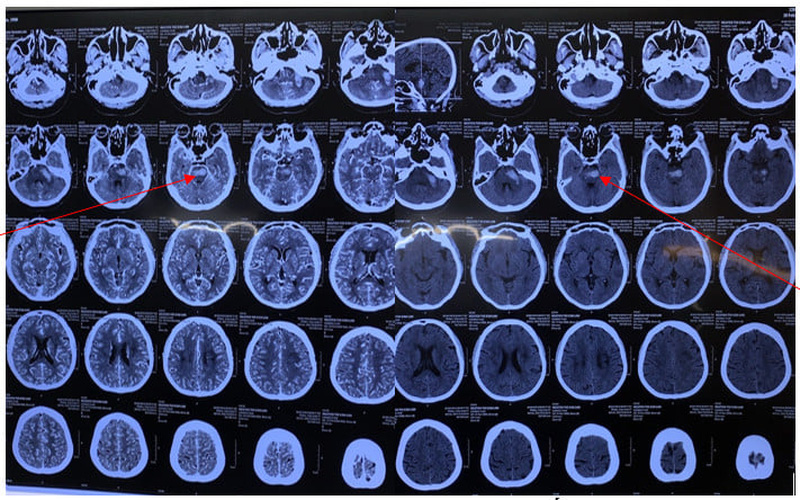

Theo thông tin từ Bệnh viện Quân y 103, bệnh nhân N.T.K.L. (64, trú tại Mộ Lao, Hà Đông, Hà Nội), có tiền sử tăng huyết áp, điều trị không thường xuyên. Bệnh nhân vào Khoa Cấp cứu được đặt nội khí quản, thở máy, chụp cắt lớp vi tính sọ não, test nhanh dương tính COVID-19.

Đột quỵ là bệnh phổ biến, có tỷ lệ tử vong cao, để lại nhiều di chứng nặng nề. Xuất huyết não tự phát mặc dù chỉ chiếm 10 – 20% tất cả các trường hợp đột quỵ nhưng tỷ lệ tử vong vẫn còn cao, khoảng 37,6 – 52% trong tháng đầu, phần lớn trong số đó tử vong trong hai ngày đầu; gây tàn phế nặng nề và là loại đột quỵ được đề cập đến nhiều nhất hiện nay.